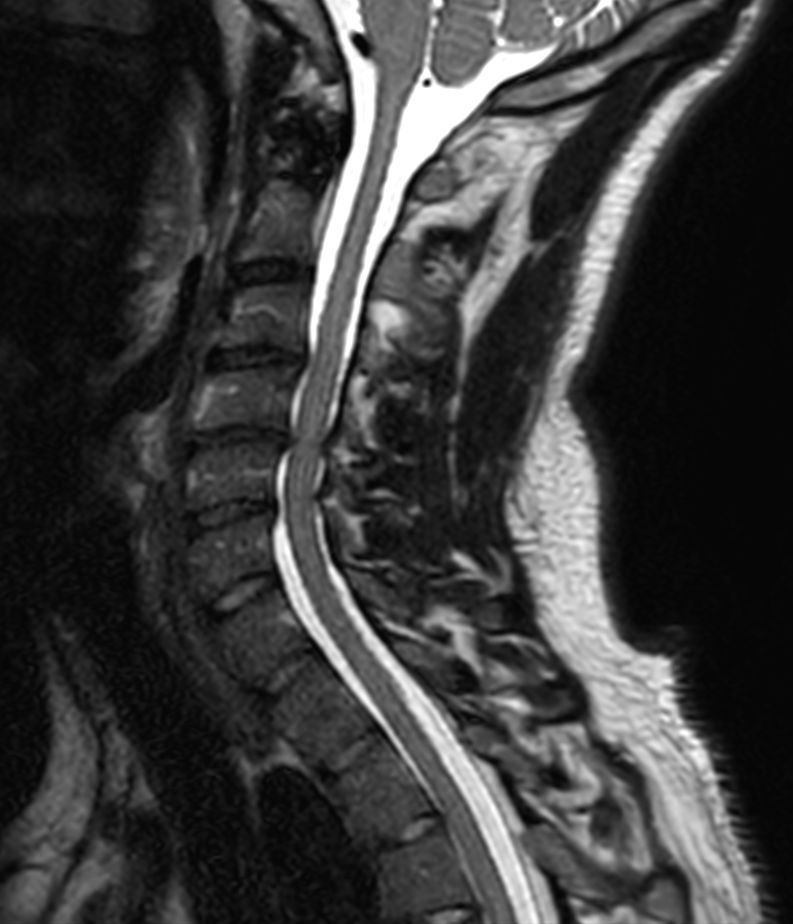

T1w TSE